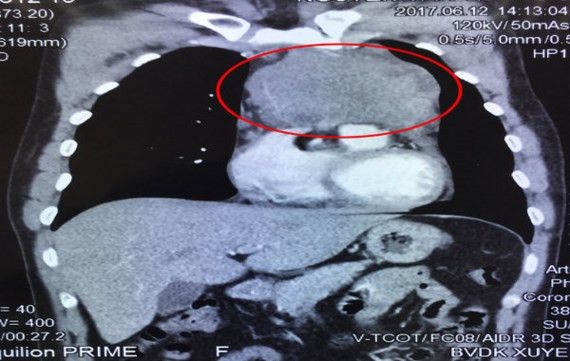

| Ảnh chụp CT khối u (khoanh đỏ) trong lồng ngực bệnh nhân trước phẫu thuật |

Khối u này đã xâm lấn rộng vào màng ngoài tim, tĩnh mạch vô danh, thần kinh hoành bên trái, động mạch phổi và lan ra sau dính vào động mạch chủ ngực xuống.

Bệnh nhân là anh N.V.Q. (38 tuổi, ngụ tại huyện Củ Chi, TPHCM) nhập viện trong tình trạng ho dai dẳng, tức ngực liên tục. Anh Q. đã mua thuốc bên ngoài uống trong thời gian dài mà không thuyên giảm. Sau khi thăm khám kỹ lưỡng, thực hiện chụp cắt lớp vi tính 160 lát (CT) cùng các thăm dò cận lâm sàng cần thiết khác, các bác sĩ xác định có 1 khối u xuất phát từ trung thất trước, xâm lấn rộng vào màng ngoài tim, tĩnh mạch vô danh, thần kinh hoành bên trái, động mạch phổi và lan ra sau dính vào động mạch chủ ngực xuống.